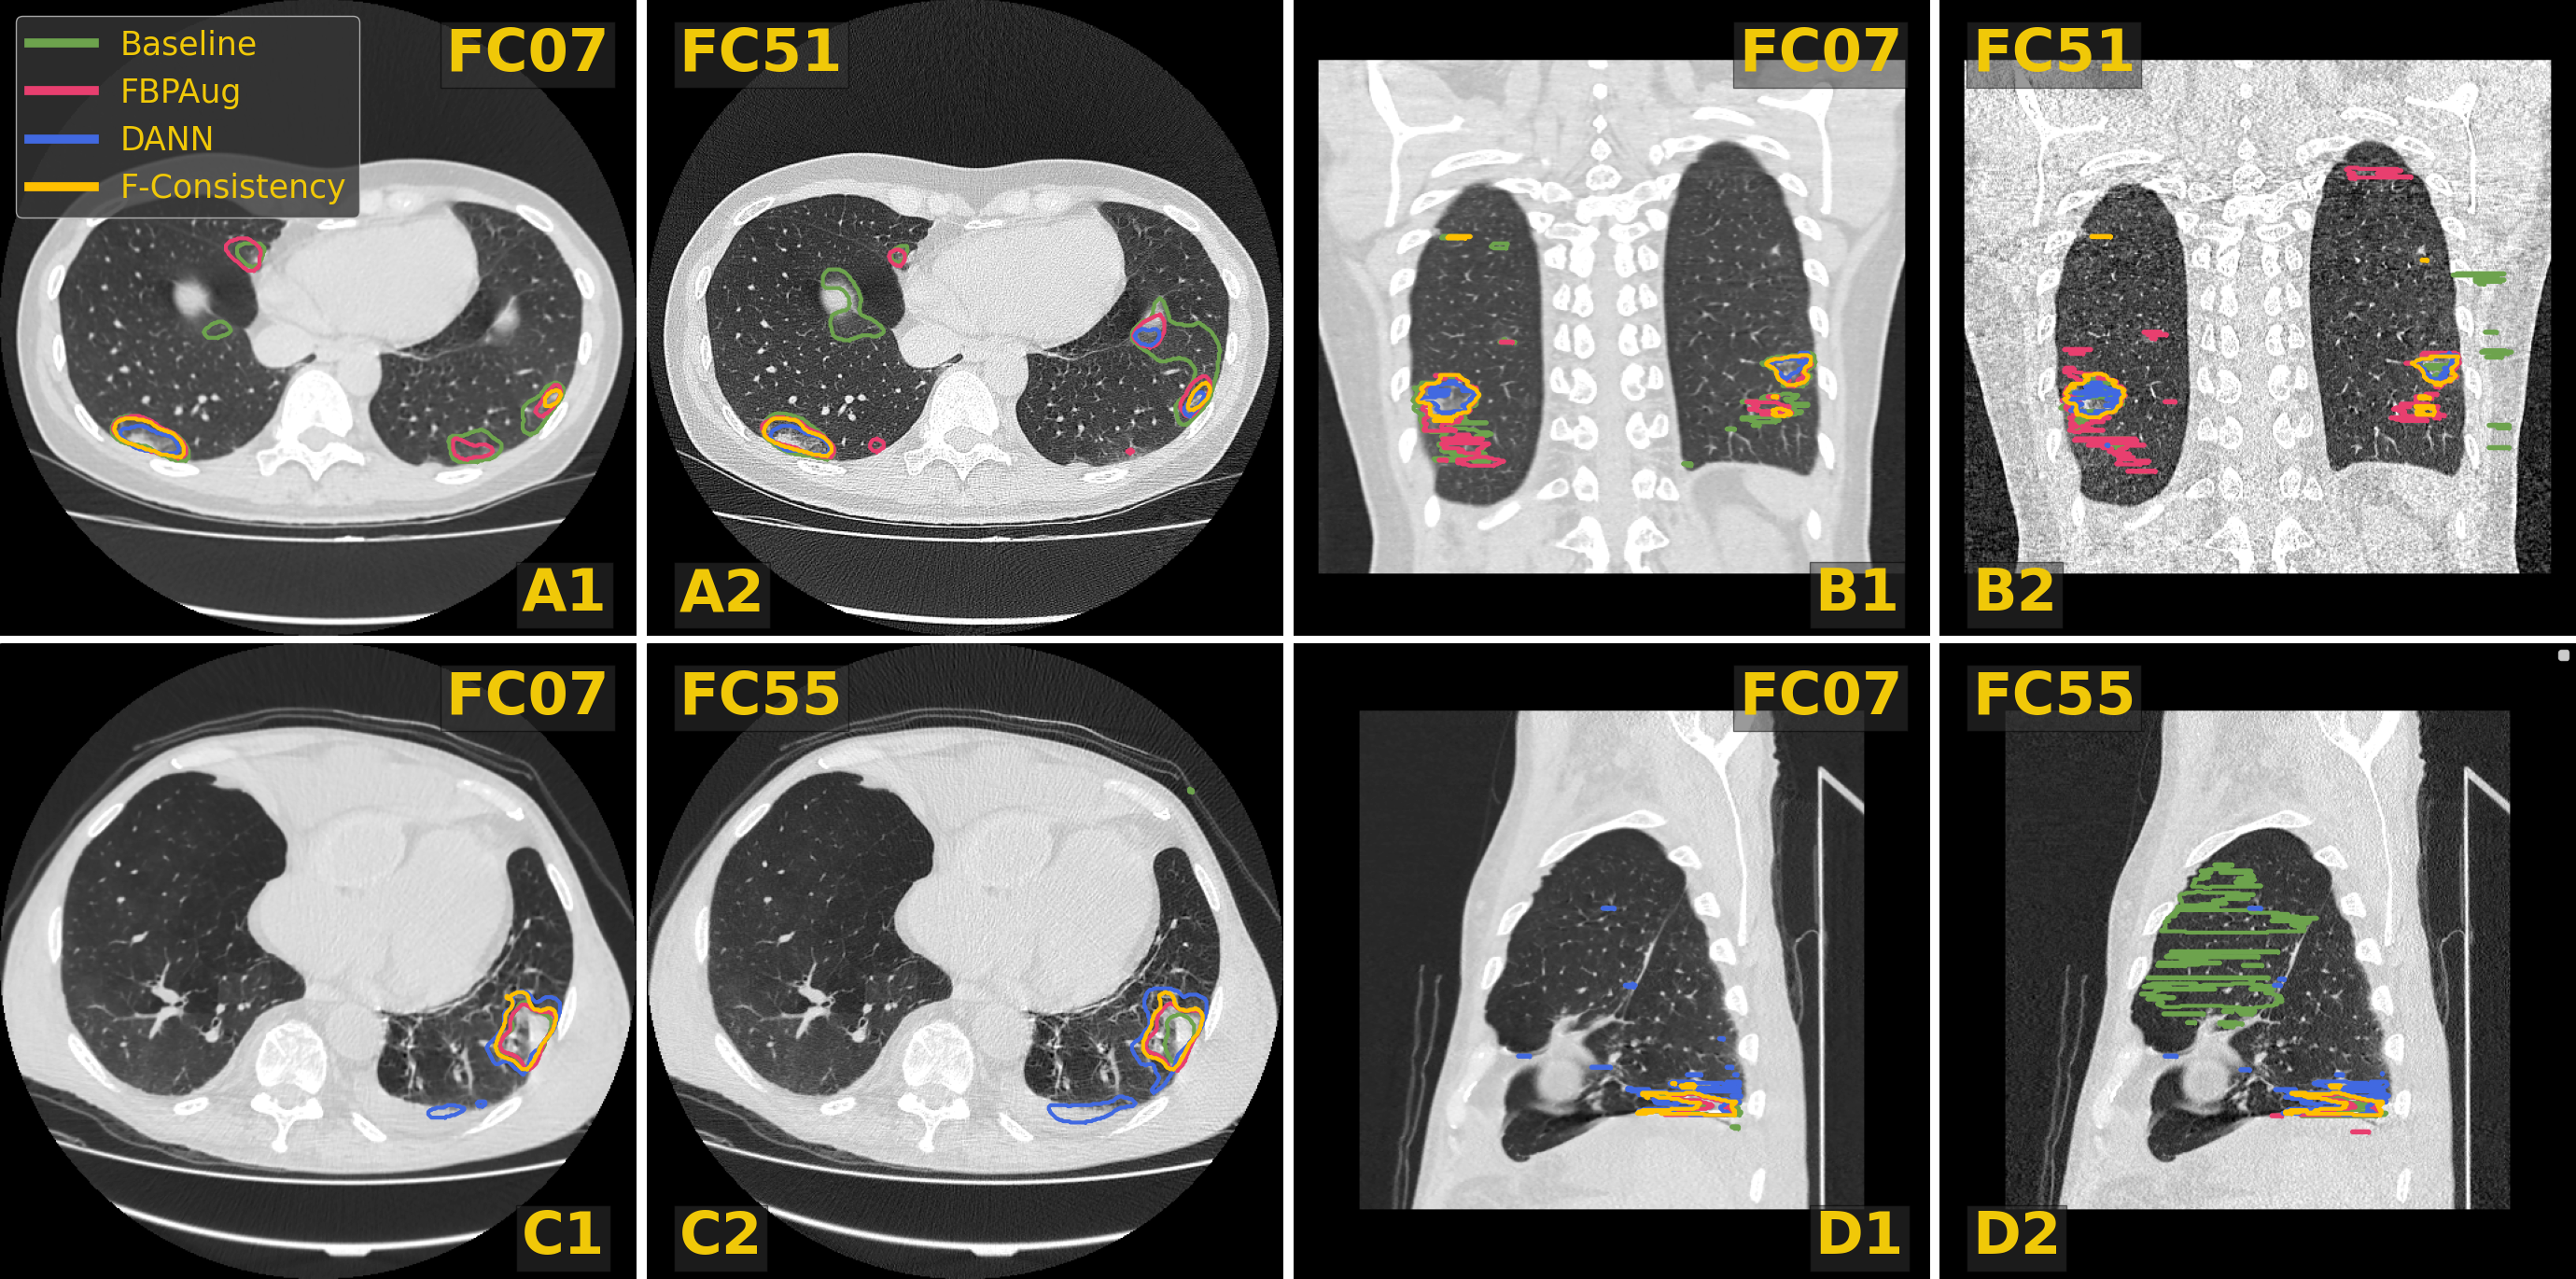

In merging a larger pool of data, the problem of domain shift arises. Domain shift is one of the most salient problems in medical computer vision (Choudhary et al., 2020). A model trained on the data from one distribution might yield poor results on the data from the different distribution. In CT imaging, one of the main sources of the domain shift is the difference in reconstruction kernels, the parameter of the Filtered Back Projection (FBP) reconstruction algorithm (Schofield et al., 2020). One could perceptually compare the same image reconstructed with two different kernels in Fig. 3, e.g., B1 and B2. For the kernel-caused domain shift, several works have shown the deterioration of the models’ quality, in lung cancer segmentation (Choe et al., 2019), and in emphysema segmentation (Lee et al., 2019).

In Fig. 3, we visualize predictions of the same four methods on the paired images from the Paired-private dataset. For the Baseline, we observe an extreme inconsistency (Fig. 3, A) and massive false positive predictions in healthy lung tissues (Fig. 3, D) and even outside lungs (Fig. 3, B). For the adaptation methods, their predictions are visually more consistent inside every pair, which aligns with the consistency scores in Tab. 3. Despite the high consistency scores, FBPAug and DANN output perceptually more aggressive predictions. FBPAug predicts motion artifacts near the body regions (Fig. 3, A) and triggers similarly as the baseline on, most likely, healthy lung tissues (Fig. 3, B). DANN is more conservative but triggers on the consolidation-like tissues (Fig. 3, C and D). However, without the ground truth annotations on the paired data, we refer to this analysis as a discussion.